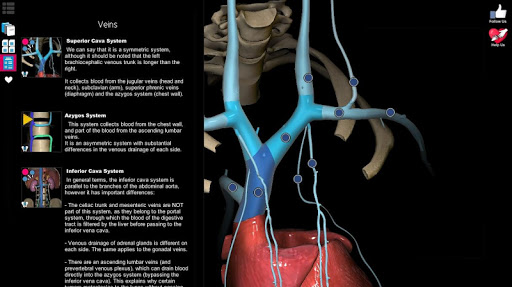

A true and totally 3D app for studying human anatomy, built on an advanced interactive 3D touch interface.

★ You can rotate models to any angles and zoom in and out

★ Remove structures to reveal the anatomical structures below them.

★ Switch on/off different anatomy systems

★ Circulation (arteries, vein and heart)